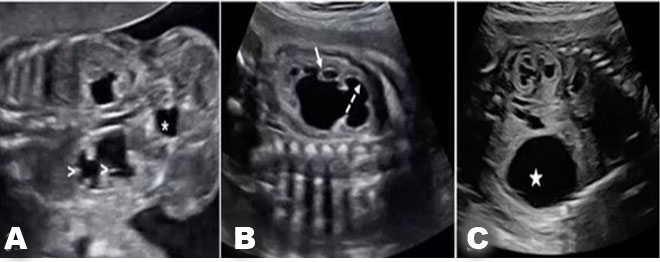

Imaging

Diagnosis of LUTO is accurately done through ultrasound with high sensitivity and specificity [28]. Lower urinary tract obstruction may present in fetuses with a dilated renal pelvis and small fluid filled areas (Figure 11). Distinctions between obstructive and non-obstructive causes can be made through echogenicity and presence of oligohydramnios [29]. Obstructions may present with a large bladder (megacystis) and dilation of urethra (“keyhole sign”) depending on location of obstruction [30]. If anhydramnios is noted on ultrasound it is associated with a higher prevalence of pulmonary hypoplasia and renal dysplasia [28]. Changes in renal parenchyma on ultrasound are also associated with a higher rate of renal dysplasia [28]. Magnetic resonance imaging is suggested if ultrasound cannot be used for assessment of genitourinary tract because of oligohydramnios. Fetal serial urine analysis will be helpful in understanding renal function and provide further information for prognosis.

Diagnostic checklist

It is important in diagnosis to visualize the bladder and kidneys assessing for any abnormalities. Identifying specific obstruction will be key in prognosis and consideration for surgical intervention (Figure 11).

Figure 10: Ultrasound images showing bilateral UPJO. Caliectasis is seen in (A) (arrows heads) and (B) (arrows), renal parenchyma is thinned. (C) Increased echogenicity in the renal parenchyma and a large urinoma (white star). Bladder (asterisk) appears normal in (B) [43]. Radiological images were obtained from open-access article distributed under the terms of the Creative Commons Attribution License (CC BY) [43].

Figure 11: Ultrasound image of a LUTO anomaly showing an enlarged fetal bladder (B) with a dilated proximal urethra (u) [43]. Radiological images were obtained from open-access article distributed under the terms of the Creative Commons Attribution License (CC BY) [43].